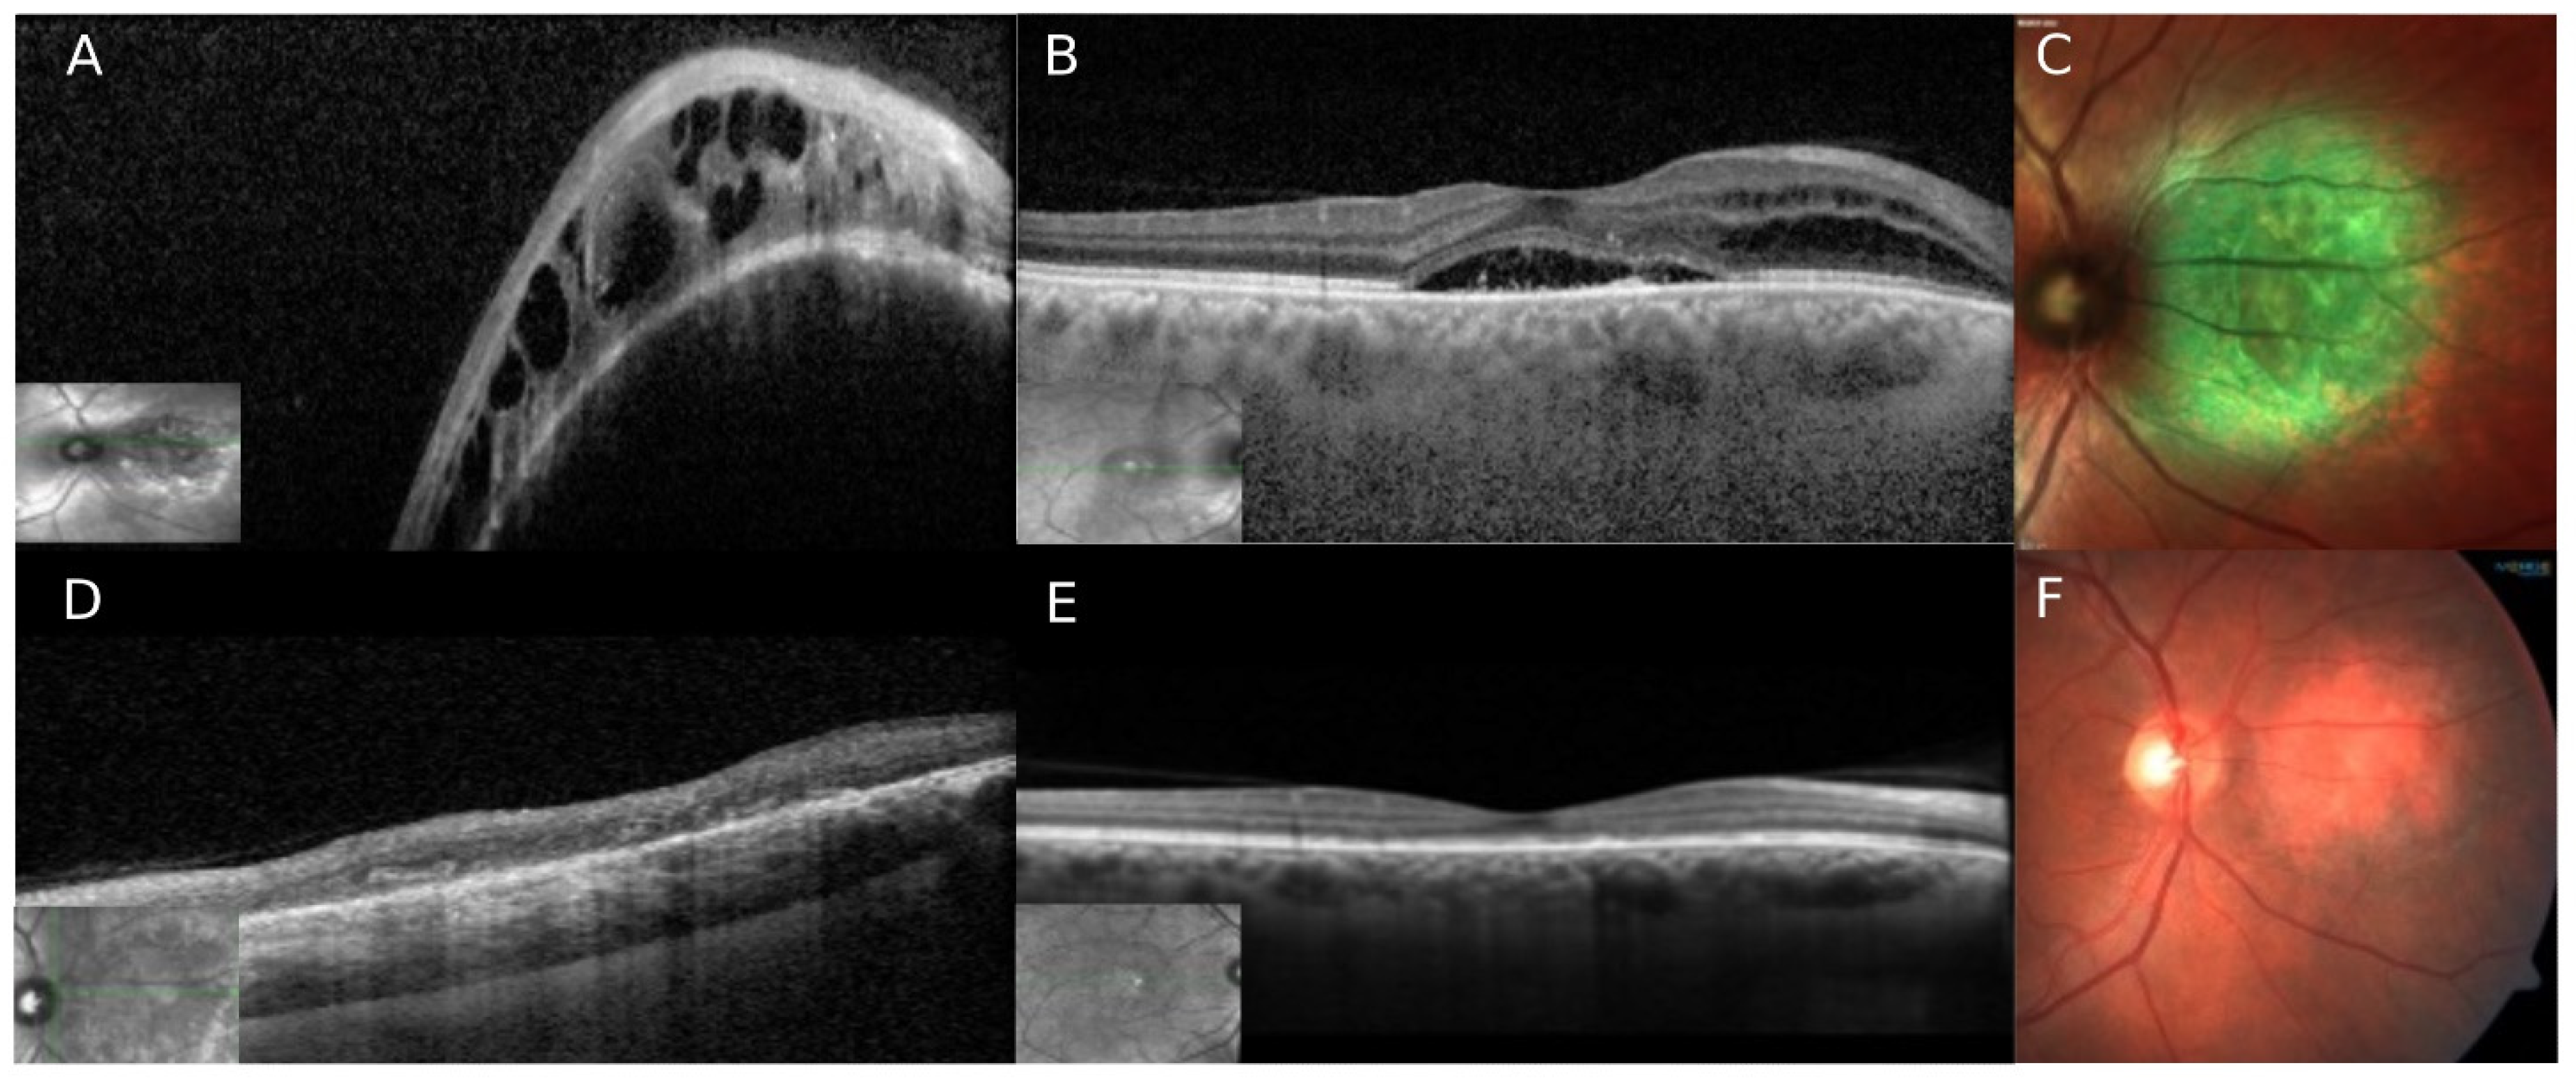

5. Case Number 4